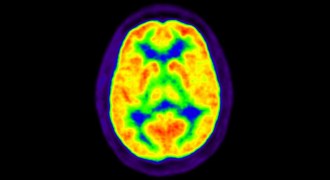

12. Neuroscience

Decoding sommeliers’ brains, one squirt of wine at a time

Researchers use a ‘gustometer’ to control wine portions in experiments comparing the brains of sommeliers and novices.